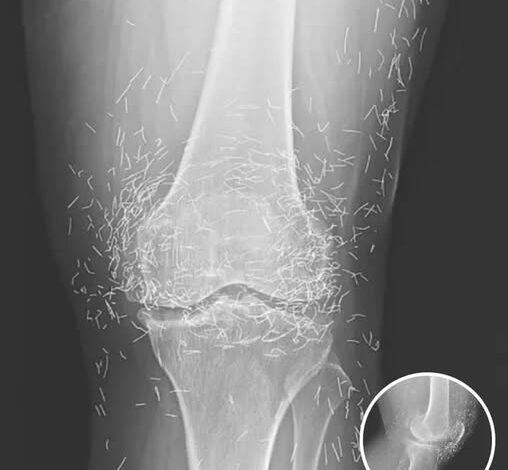

The intersection of ancient tradition and modern diagnostic medicine rarely produces an image as startling as the one that recently captivated the global medical community. When a 65-year-old South Korean woman presented herself for a routine examination to address chronic, debilitating joint pain, her physicians expected to see the standard markers of age-related wear and tear. Instead, as the X-ray film developed, they were met with a sight that seemed more akin to a piece of intricate jewelry than a human anatomy. Embedded deep within the soft tissue and synovial spaces of her knees were hundreds of tiny, shimmering gold needles, perfectly preserved in a geometric display of alternative intervention. This case, later documented in the New England Journal of Medicine, has ignited a fierce debate over the boundaries of traditional healing and the hidden risks of permanent “embedded” therapies.

Beyond the immediate risk of infection, these “shimmering” knees present a massive obstacle to modern diagnostic technology. Metal of any kind is notorious for creating “artifacts” on an X-ray or CT scan—streaks of white light that obscure the very anatomy a doctor is trying to see. In this woman’s case, the sheer density of the needles made it nearly impossible for physicians to accurately assess the current state of her osteoarthritis. The very “cure” she sought had created a visual shield that hid the progression of her disease.

However, the most life-threatening risk involves the gold standard of modern diagnostics: the MRI (Magnetic Resonance Imaging). An MRI machine is, essentially, a massive and incredibly powerful magnet. If a patient with hundreds of metal needles embedded in their joints were to enter an MRI suite, the results could be catastrophic. The magnetic field can exert enough force to cause the metal fragments to migrate or vibrate violently within the tissue. This could lead to internal hemorrhaging, the puncturing of vital blood vessels, or severe nerve damage. In a medical emergency where an MRI might be the only way to save a life, these permanent acupuncture needles could effectively bar a patient from receiving life-saving care.